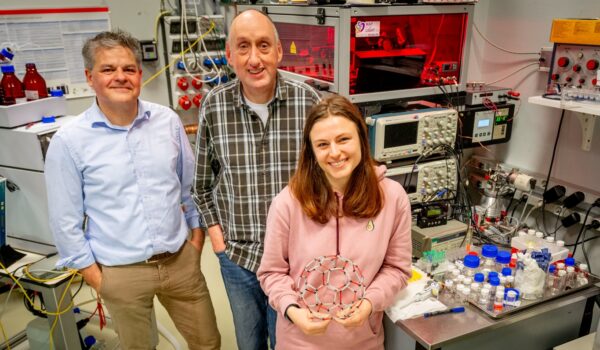

Researchers from HFML-FELIX have successfully identified molecules related to two rare genetic disorders, directly from brain tissue using a powerful infrared free-electron laser. This new analytical technique contributes to a better understanding of these diseases and may lead to faster diagnoses and more effective treatments in the future.

In his experiments, HFML-FELIX researcher Jelle Schuurman has looked at two metabolic diseases – pyridoxine-dependent epilepsy and glutaric aciduria type 1 – that prevent a specific substance from being processed properly, namely the substance lysine. The consequences of this disturbed process are particularly visible in the brain. Therefore, researchers want to understand this process as complete as possible. Which substances accumulate, for example? And by extension: what do we see when we apply certain treatments? What changes then?

In this research, molecules in a piece of mouse tissue were first mapped using a UV laser. Then FELIX was used to identify molecules most closely correlated to the studied genetic disorders. Nowhere else in the world has that been achieved in this way before, Schuurman explains. ‘Being able to identify molecules directly from biological tissue, in low concentrations and without having to do an extraction or purification, is completely new. We did not get it right immediately either, but we are very enthusiastic that we eventually succeeded. We are getting a lot of positive reactions from colleagues in the research field.’